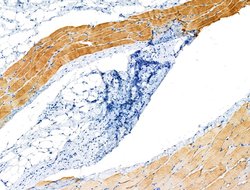

Invitrogen™ Phospho-ASAP2 (Ser701) Polyclonal Antibody

Antibody detects endogenous levels of ASAP2 only when phosphorylated at Ser701.

| Immunohistochemistry (Paraffin), Western Blot | |

| A synthesized peptide derived from human ASAP2(Accession O43150), corresponding to amino acid residues around phosphorylated Ser701. | |